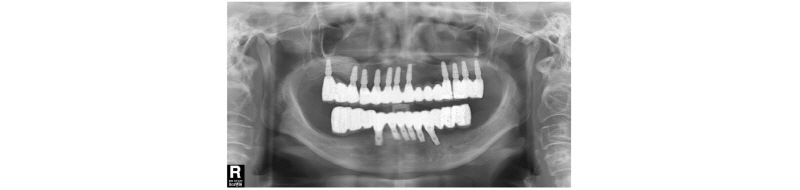

전악 발치 후 하악에는 이공 사이에 6개의 임플란트를 상악에는 8개의 임플란트를 식립하기로 계획하였으나 조기 부하에 의한 임플란트 실패가 우려되어 상악에는 11개의 임플란트를 수술하고 그중 5개의 임플란트를 이용하여 상악 하악 모두 조기 부하를 시도하였다(Fig. 2, 3). 2010년 9월 임플란트 식립과 봉합 후 픽업 임프레션 코핑을 이용해서 인상을 채득하고 상악의 경우 임시치아를 1-piece로 만들었고(Fig. 4) 하악의 경우 구치부의 캔틸레버가 길어서 레진으로 만드는 임시치아는 힘을 버틸 수 없으므로 바로 기성 어버트먼트에 PFM을 1-piece로 제작하여 술 후 2주 후에 부착했다(Fig. 5). 25, 26, 27은 상악동 거상술과 동시에 픽스쳐를 식립하고 묻어두었다. 5개월 뒤 25, 26, 27번 임플란트의 2차 수술을 시행하였고, 처음의 우려와 상관 없이 조기 부하에 사용했던 5개의 임플란트는 모두 골유착에 성공하였다. 단 하악 좌측 견치 부위의 임플란트가 조기 부하의 영향으로 골유착이 양호하지 않은 것으로 보였으나 환자는 불편감이 전혀 없었고 하악의 보철이 1-piece로 제작되어 있었기 때문에 환자에게 고지 후 그대로 유지하기로 하였다. 상악 좌측 구치부의 2차 수술 후 2개월을 더 치유시킨 후 수술한 지 7개월 만에 2011년 4월 상악 최종 보철을 완성하였다(Fig. 6, 7).

상하악 무치악 환자에서 상악에 11개의 임플란트를 수술 한 후 5개의 임플란트를 사용하여 고정성 임시보철물을 만들고 즉시 부하를 가하였으며 하악에서는 6개의 임플란트를 양쪽 이공 사이에 식립하고 제 1 대구치까지 연장되는 캔틸레버 보철물을 만들어 즉시 부하를 가했다. 치유되는 동안 좌측 최후방에 식립된 임플란트만 골유착에 실패했고 나머지 5개의 임플란트는 정상적으로 치유되었다. 상악의 경우 즉시 부하에 사용되었던 5개의 임플란트를 포함해 11개의 임플란트가 모두 골유착에 성공했다.

Sertqoz와 Guvener는 캔틸레버와 임플란트의 길이가 임플란트 유지 고정성 보철물에 미치는 영향에 대한 유한요소분석 결과에서 부하를 받는 쪽의 가장 원심측 임플란트가 가장 많은 스트레스를 받는다고 보고하였다3. 이 증례에서도 최후방 임플란트 한 개가 골유착에 실패했으나 염증소견을 보이지 않고 즉시 부하 후에 사용하는데 불편감이 없어 그대로 유지하고 관찰하였으며 7년의 기간 동안 그대로 잘 유지되었다(Fig. 8, 9).